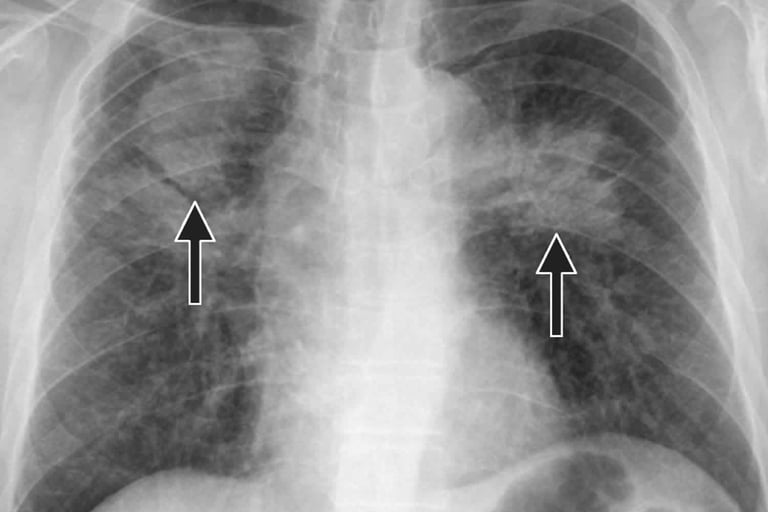

Jednym z najświeższych dokumentów jest raport „Effects of Welding on Health 2023” opracowany przez AWS i inne ośrodki — w którym zauważono między innymi, że spawacze wykazują obniżoną funkcję oddechową, a stężenia tlenków chromu (Cr VI) i manganu są podwyższone w środowisku pracy. Link: aws-p-001-delivery.sitecorecontenthub.cloud

W praktyce oznacza to, że choć czujesz się „w porządku”, Twoje płuca mogą już pracować z gorszą efektywnością — szczególnie jeśli spawasz codziennie, przez lata.

Inne badania wskazują, że nawet klasyczne testy spirometryczne mogą nie wychwycić wczesnych zmian — nowe metody, jak oscylometria czy biomarkery krwi (np. markery zapalne), wykazują subtelne uszkodzenia u osób, które klasycznie „mieściły się w normie”. aws-p-001-delivery.sitecorecontenthub.cloud

Badania wskazują, że w spawalnictwie są ekspozycje na lotne związki organiczne (VOCs) i ultradrobne cząstki, które mogą przenikać głęboko do płuc — a współczynnik stanów zapalnych może rosnąć. Link: aws-p-001-delivery.sitecorecontenthub.cloud

Istnieje także związane ryzyko zwiększonej podatności na zakażenia pneumokokowe u spawaczy — z kilku analiz wynika, że choroby układu oddechowego częściej dotykają osoby, które pracują z metalami spawalniczymi. Link: aws-p-001-delivery.sitecorecontenthub.cloud